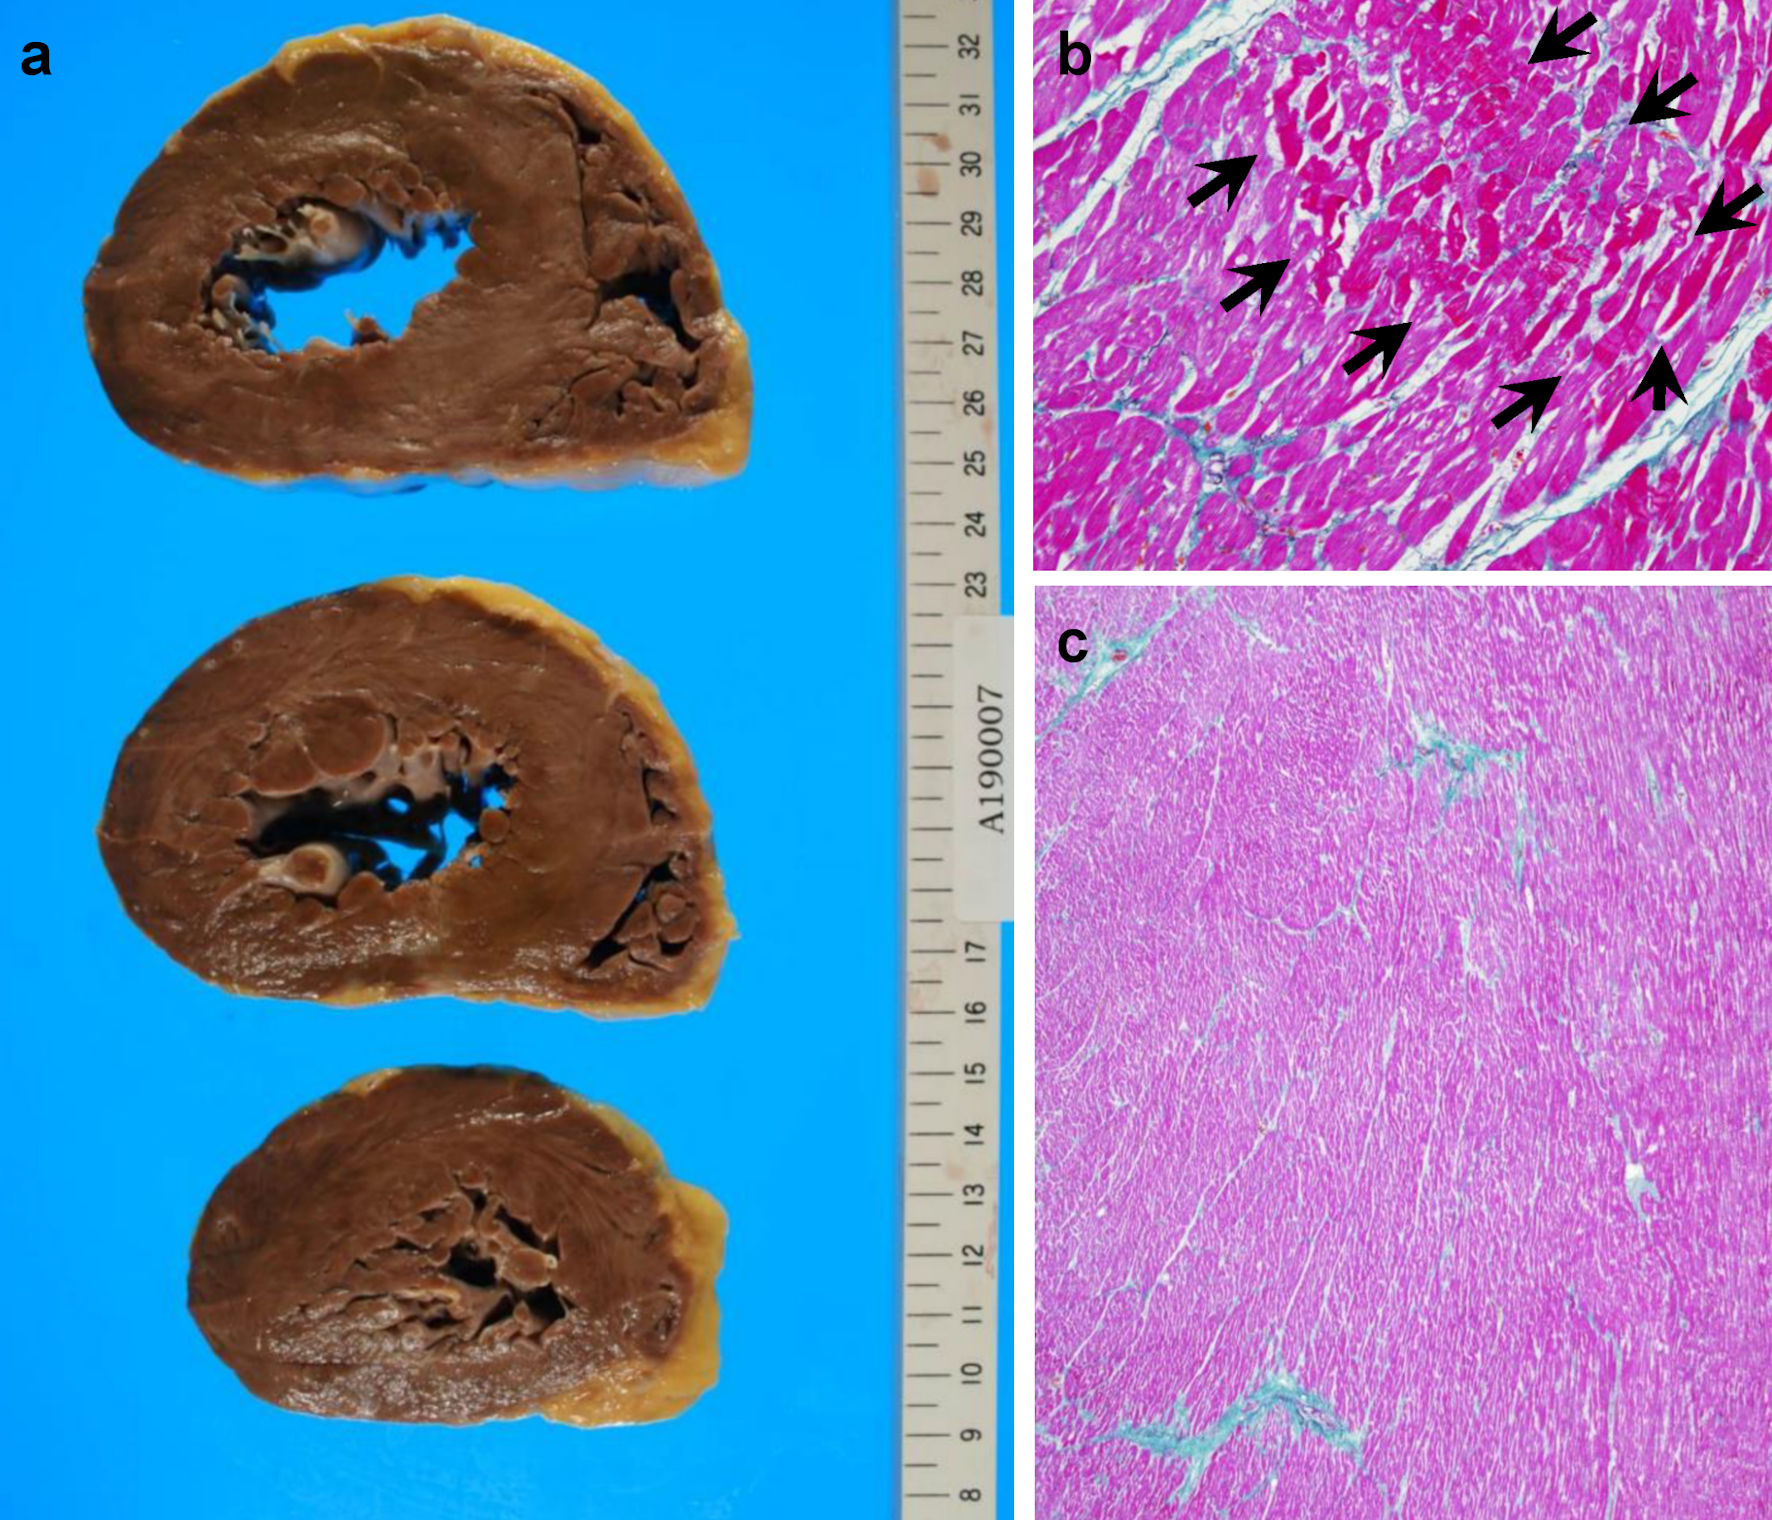

The hematoxylin and eosin (H&E)-stained section findings revealed no HL recurrence but invasive urothelial carcinoma with high-grade dysplasia (latent cancer) in the left renal pelvis (Fig. 4a-c), as well as infiltration around the inferior vena cava, lungs, and left kidney. Lung histology revealed some cancer cells and a small number of thrombi (Fig. 5a), with fibrocellular intimal proliferation of small pulmonary arteries (Fig. 5b). The heart showed marked left ventricular hypertrophy (Fig. 6a), while histology showed focal myocardial necrosis (Fig. 6b, indicated by the arrows in the H&E-stained section) and mild fibrosis around the vessels with Masson’s trichrome staining (Fig. 6c, shown as the blue staining). The primary causes of mortality, in this case, were respiratory and heart failure due to PTTM.

![]() Click for large image | Figure 4. Patient’s autopsy findings of the kidney. (a) Gross findings of the left kidney. (b, c) Urothelial carcinoma of the renal pelvis in hematoxylin and eosin-stained sections. |

![]() Click for large image | Figure 6. Patient’s autopsy findings of the heart. (a) Gross findings of the heart. (b) Focal myocardial necrosis (arrows) in the hematoxylin and eosin-stained section. (c) Mild fibrosis in myocardial tissues around vessels, shown as blue Masson’s trichrome staining. |